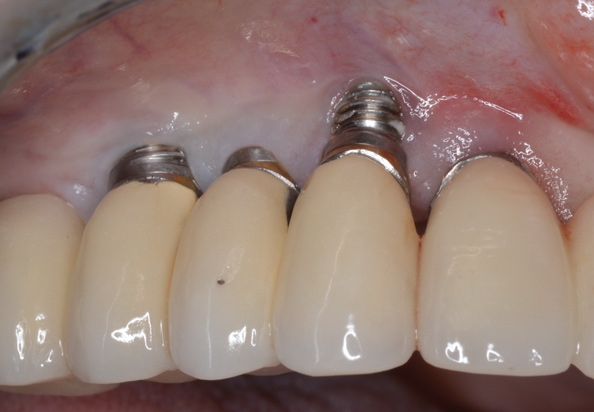

(3.) Two implants removed with two separate techniques. The narrow implant had an abutment that was easily removed, making it possible to engage with a reverse torque device. The wider implant contained a fractured abutment screw and required removal with a trephine. Its wider platform dictated that the trephine fit over this portion, and the osseointegrated bone can be seen attached to the explanted fixture.

Figure 3